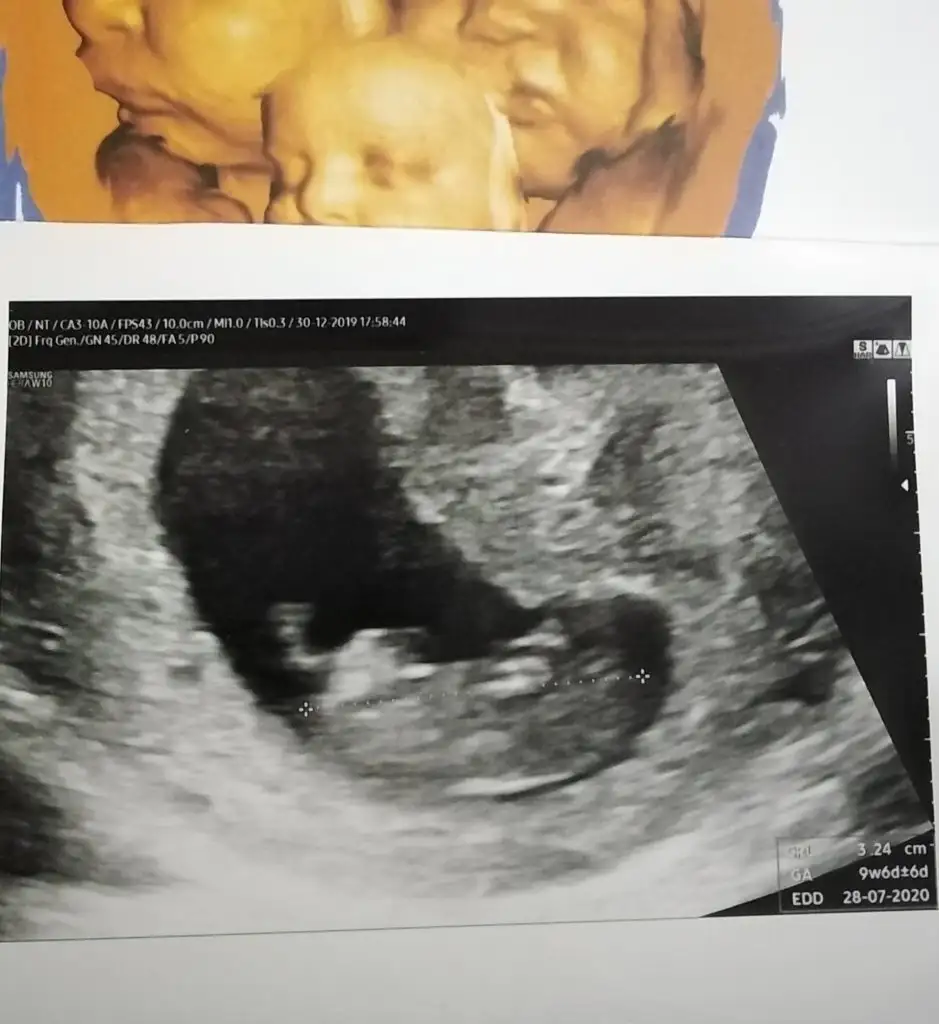

Usg göremedim 11 yada 12 hafta olmalıBen de 20 haftalik hamileyim dr kiz diyor ama hala emin degil cunku kucukte olsa bir cikinti hala var mun teorisine gore yukari dogruysa erkekmis bizimki yukari dogru fakat dr kiza daha cok benziyor dedi

Bacak arasi ultrasin goruntusu almadi dr ama drun ve benim.gordugum bir cikiti vardi ve yukari dogruydu fakat dr bunun pipiye benzemedigini kizlarda boyle cikintilar olabildigini nub teorisini onunda duydugunu ama.boyle birsey olmadigini soyledi ve bebisimin daha cok kiza benzedigini buyuk ihtimalle.kiz oldugunuda soyledi bunlari 12_18 haftalar arasi konustuk 19.haftada son kez sordum dr net goremiyorum ama kiz gibi dedi suan 20 ye girdim artik sormuyorum pes ettimUsg göremedim 11 yada 12 hafta olmalı

Siz ankete oyunuzu kullandınızmı çünki ben size tahmin etmedimBacak arasi ultrasin goruntusu almadi dr ama drun ve benim.gordugum bir cikiti vardi ve yukari dogruydu fakat dr bunun pipiye benzemedigini kizlarda boyle cikintilar olabildigini nub teorisini onunda duydugunu ama.boyle birsey olmadigini soyledi ve bebisimin daha cok kiza benzedigini buyuk ihtimalle.kiz oldugunuda soyledi bunlari 12_18 haftalar arasi konustuk 19.haftada son kez sordum dr net goremiyorum ama kiz gibi dedi suan 20 ye girdim artik sormuyorum pes ettim

Normal ultrason resimleri var ama bacak arasindan tek 1 foto bile cekmedi drSiz ankete oyunuzu kullandınızmı çünki ben size tahmin etmedimve bazı drlar nub oldugunu söylüyor hatta yabancı drlar daha çok

En son goruntusu bu ama burda da birsey belli olmuyorSiz ankete oyunuzu kullandınızmı çünki ben size tahmin etmedimve bazı drlar nub oldugunu söylüyor hatta yabancı drlar daha çok

Nub olmaz ama bacak arası boş cnmBurada 16 haftalik tam.olarak nasil anladiniz peki

Demekki cikintisi git gide kuculerek kaybolucakNub olmaz ama bacak arası boş cnm